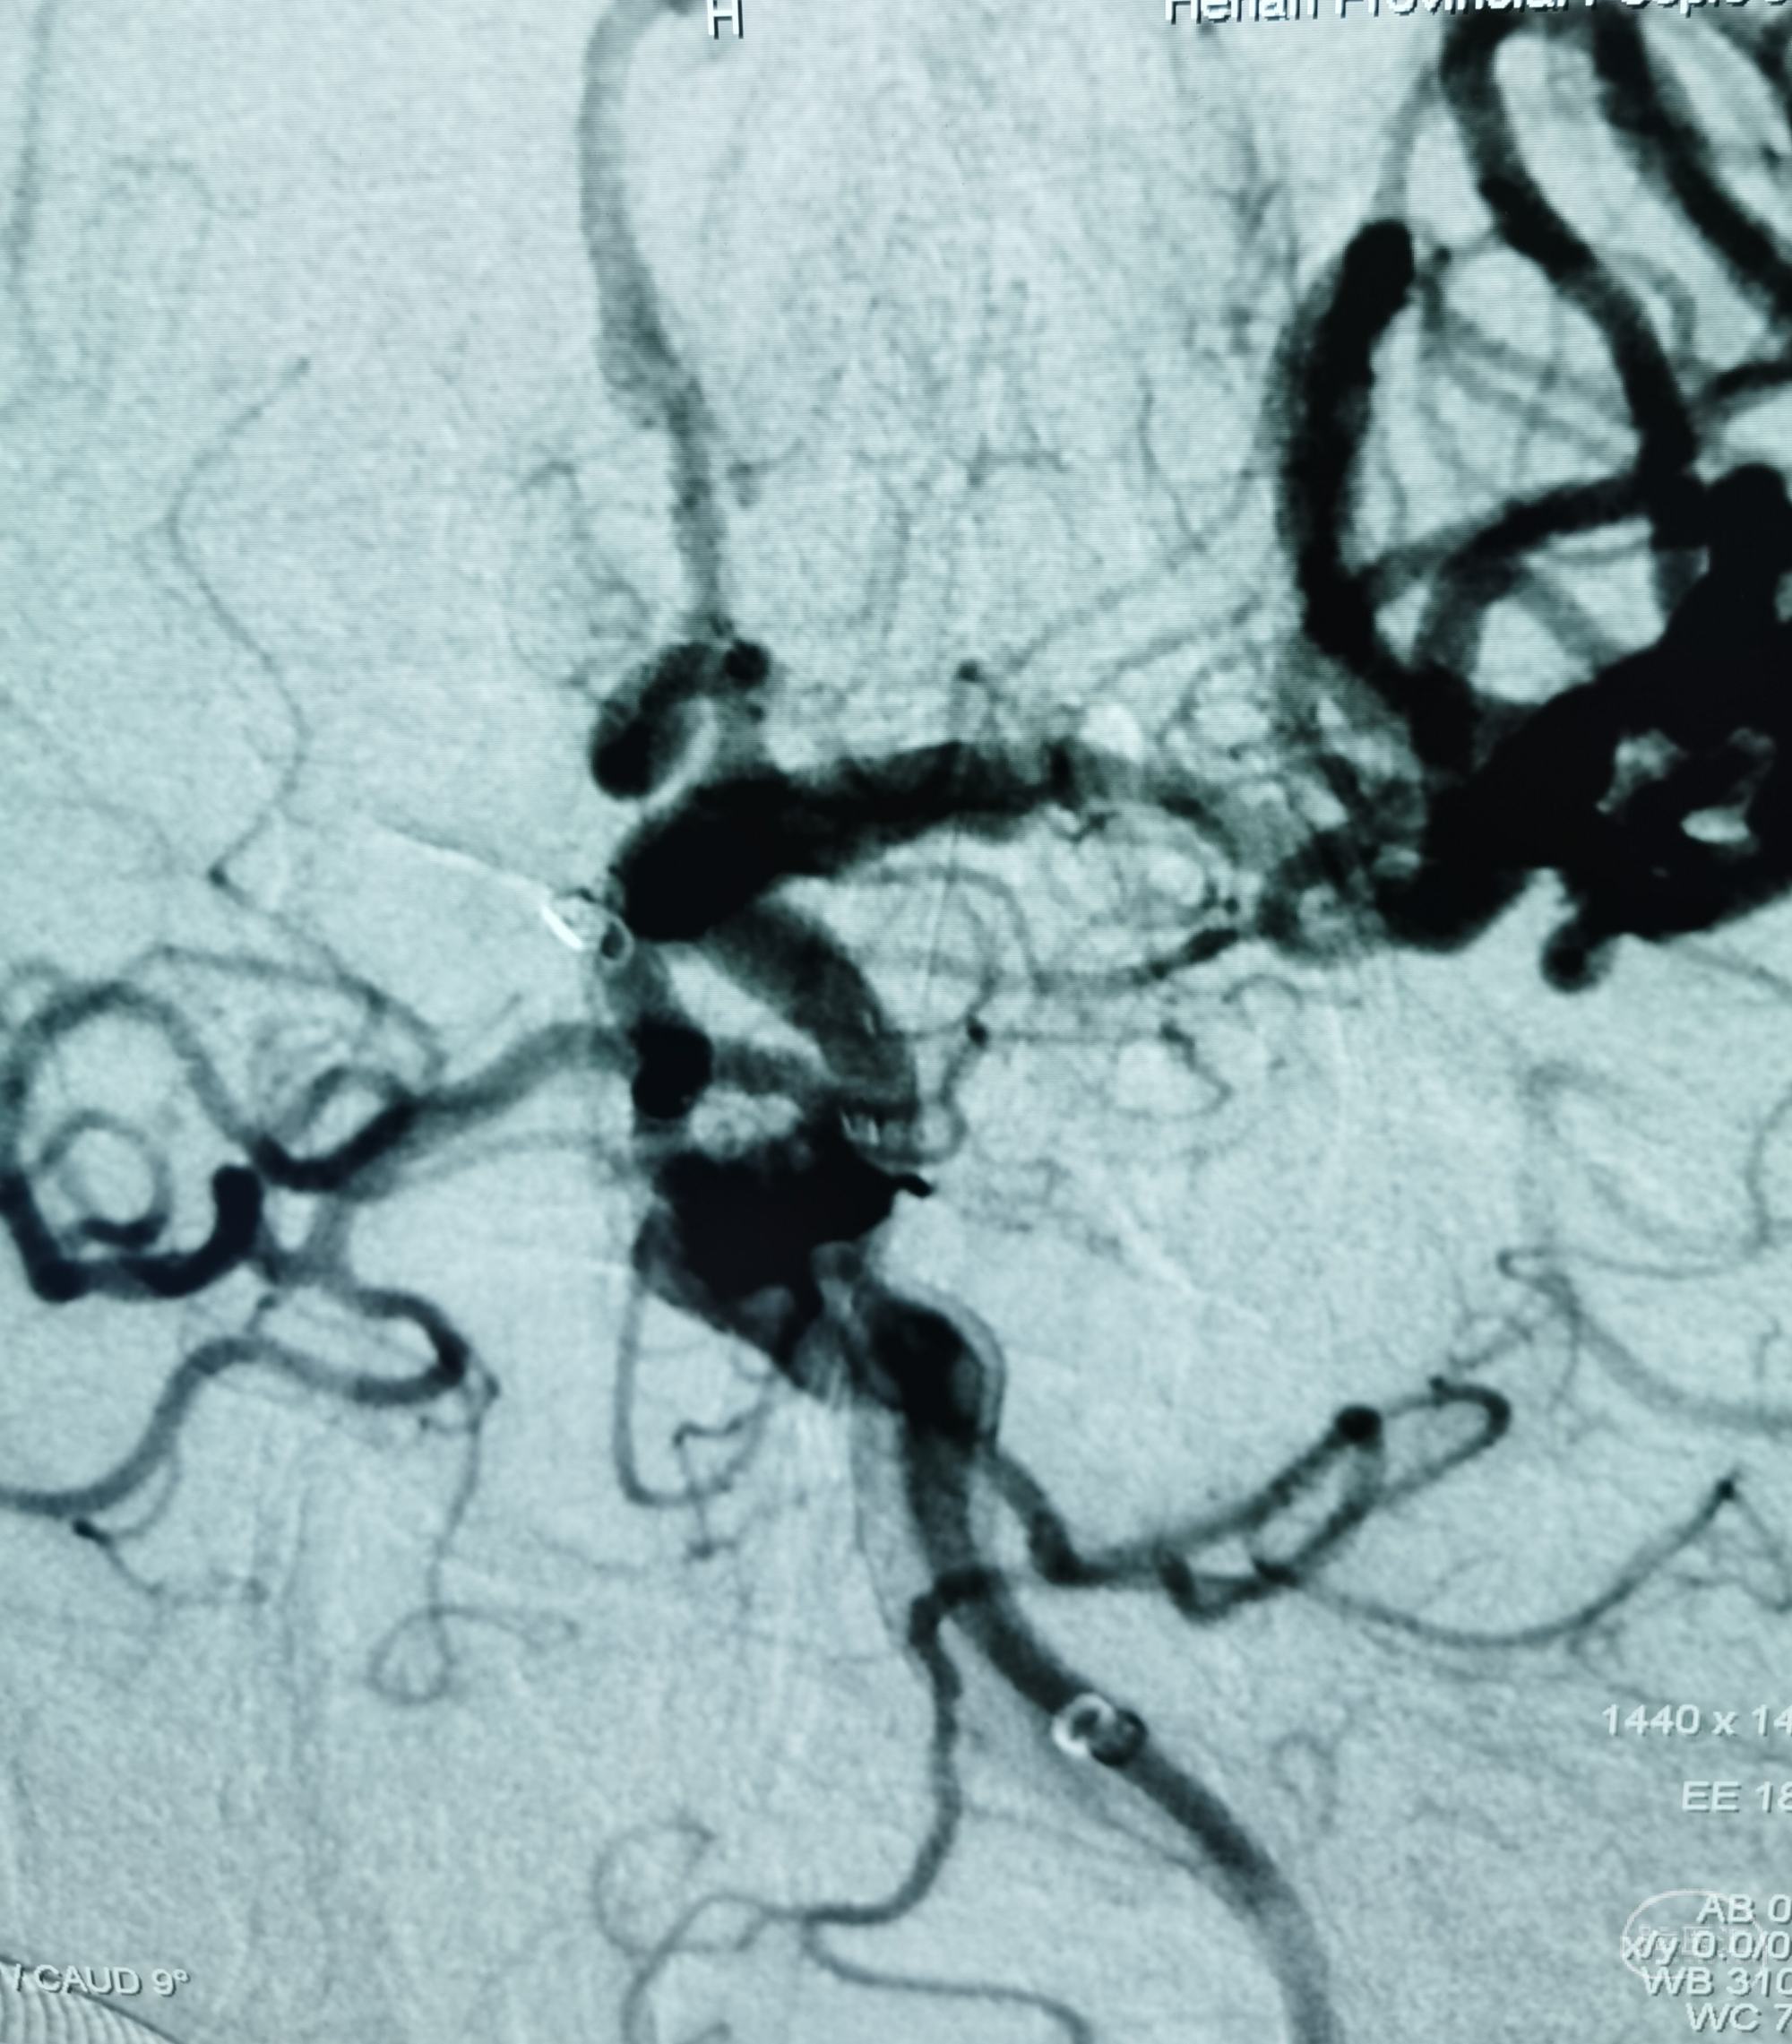

DSA:左侧大脑中动脉、大脑前动脉闭塞,烟雾样血管形成。

颞浅动脉未向颅内代偿。

行颞浅动脉-M4端侧吻合。

吻合14针。

荧光造影示:吻合桥动脉通畅。